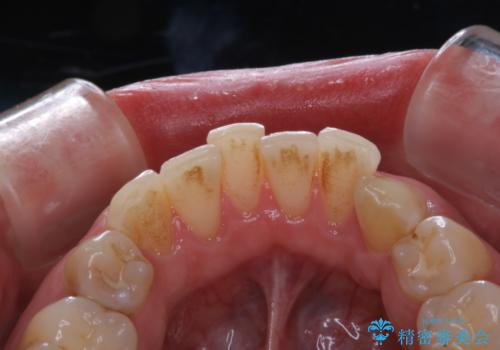

- 歯磨きをしても取れない汚れが気になるとのことで来院されました。PMTC60分コースを行いました。

着色や歯石は歯みがきで落とすことはできません。誤ったセルフケアを行うと、逆に歯の表面を傷つけてしまったり、トラブルを起こすこともあります。

着色や歯石が付着したままだと、居心地のよくなった細菌たちが口の中の栄養をたっぷり摂ってさらに付着しやすい状態となります。